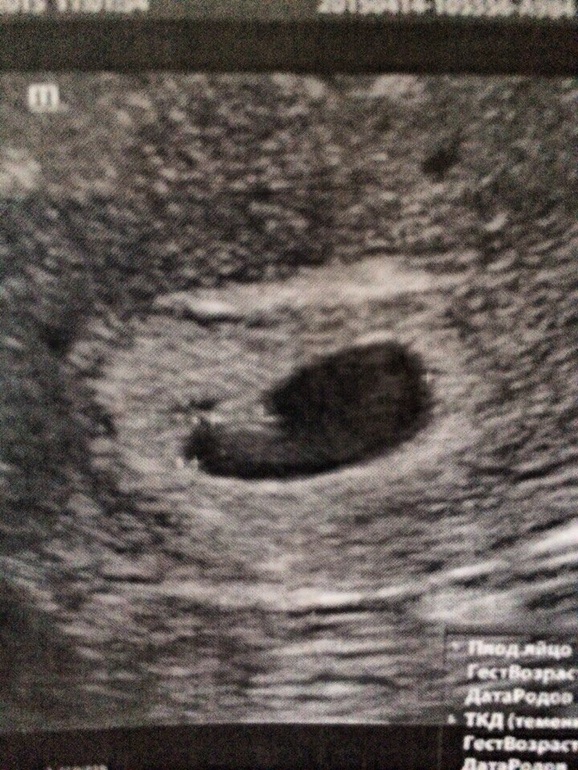

А теперь мой рассказ, пришла сегодня с утра на приём к Г. просидела под дверью 2 часа ( это при том что передамной была всего 1 девушка) . Зашла к ней и говорю я к вам в первый раз после родов и я беременная ..... Она на меня смотрит и говорит сколько прошло после родов, говорю пол года , и вы будете рожать !!!!!! Я ей говорю, да .... Карочи пыталась она меня запугать и тем что организм слабый и что тяжелое положение в стране, я не вилась выбросила направления не УЗИ и ушла. Пришла на узи попала без очереди, зашла в кабинет , легла на кушетку начался осмотр, передамной большой экран и я вижу на нём чёрной пятно и в нём бьётся маленькая точечка( я плохо слышала что врачь мне говорила, я просто понимала что это маленькое сердечко бьётся во мне , и разревелась ) она потом мне рассказала что по УЗИ срок 6 недель и всё хорошо отслойки нет . Я с улыбкой до уше прихожу к Г. Она мне опять туже песню, а может вы ещё подумаете и т д. тут в кабинет зашол мой муж и говорит , мы уже решили и будем рожать, она тяжело вздохнула и говорит приходите в четверг будем становится на учёт . Выписала утрожестан 100 2 р. в день , фолевую кислоту и витамины для беременных . Девочки я до сих пор не могу понять что это всё происходит со мной, ещё полтора года назад я об этом могла только мечтать )))